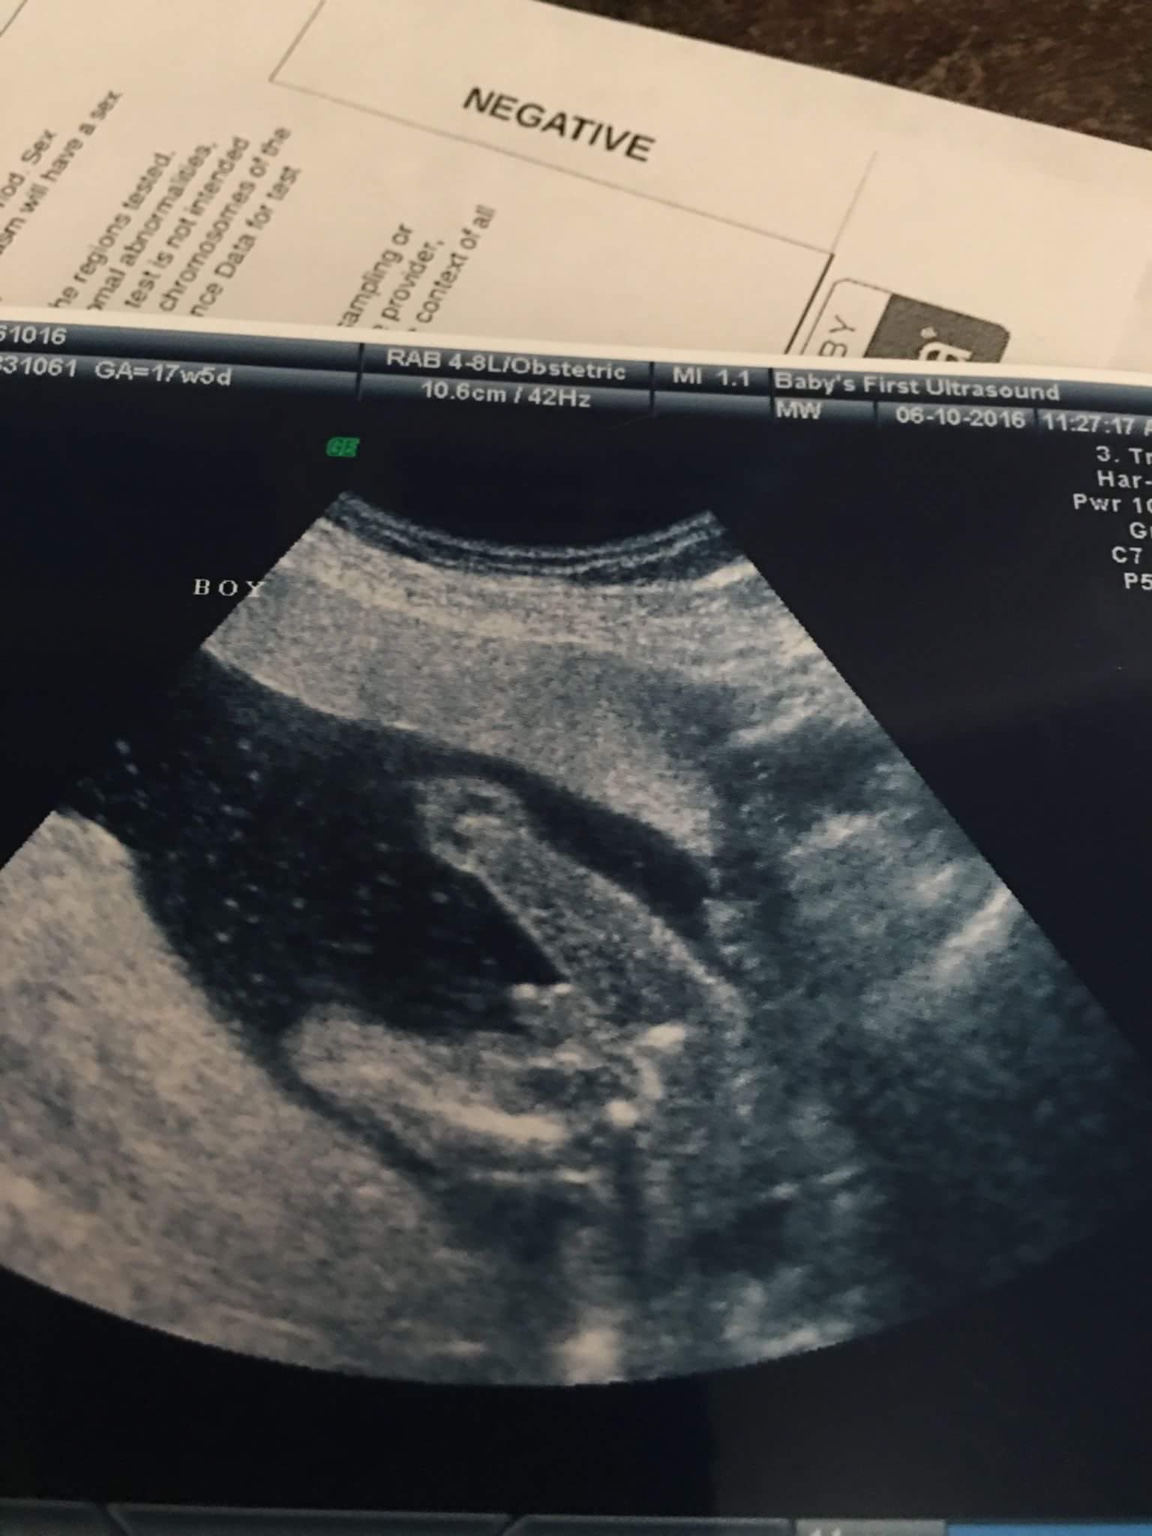

I was told a girl but from the picture it is kind of hard to see where it could be a girl.

so maybe a boy?

What would mine be?Attachment 31813Attachment 31814